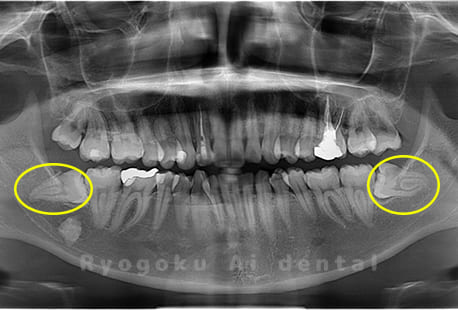

斜めに生えている親知らず

親知らずが斜めに生えて隣の歯にぶつかって圧迫してしまうタイプです。

このタイプが最も多いです。このタイプは虫歯になりやすいだけでなく、隣の歯を圧迫し、咬み合わせや歯並びに影響が出る場合もあるので抜歯をおすすめします。